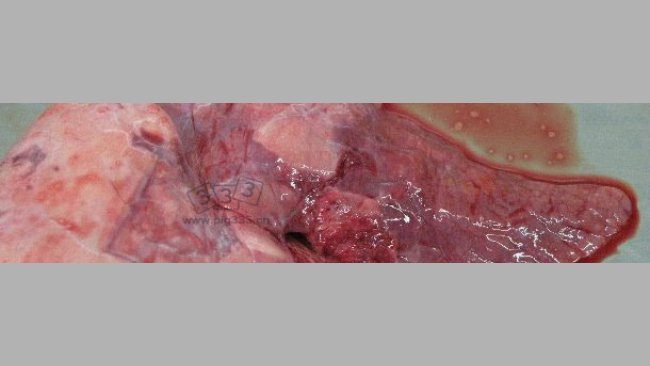

育肥猪在出栏阶段常会出现呼吸系统症状,此时抗生素处理的效果很差。但是,像本文中病毒混合感染可能性的增加就很少见了。